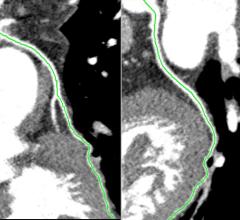

March 24, 2015 — A new study published online in the journal Radiology found a substantial gap between patient…